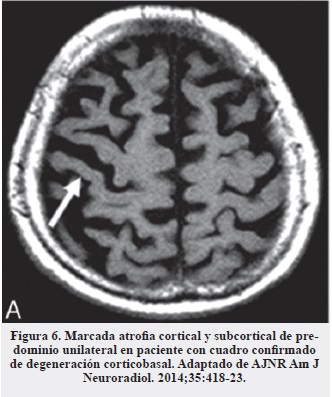

En el diagnóstico diferencial con degeneración corticobasal es importante buscar la atrofia cortical marcada unilateral característica de esta entidad (Figura 6) (17, 19) y de las afasias primarias progresivas y ausentes en la PSP, en las que la atrofia es más generalizada (17).